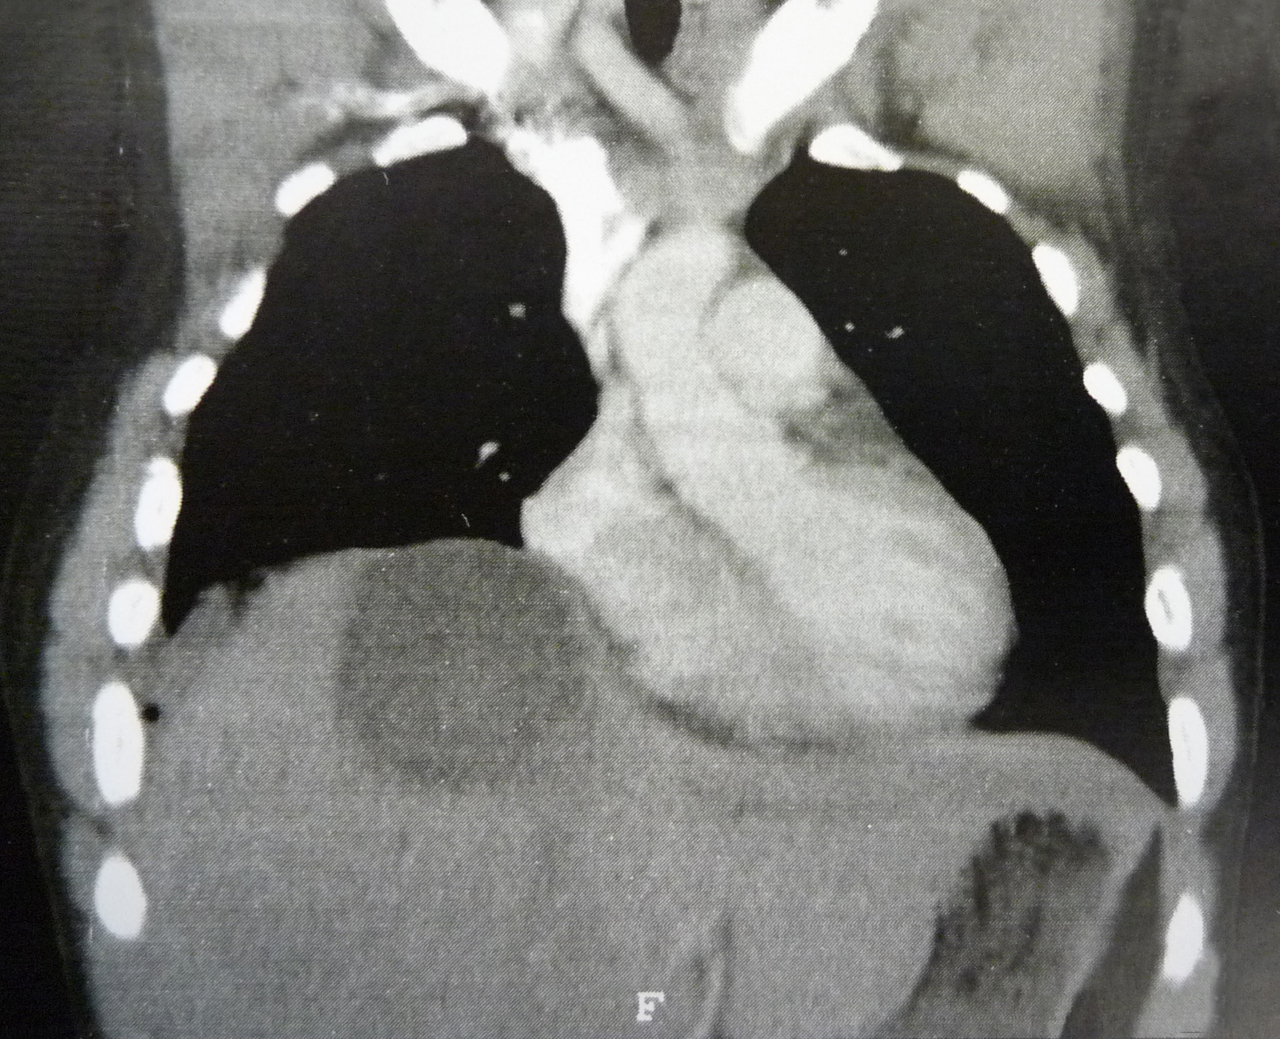

Quel est votre diagnostic ? Abcès amibien du foie Il s'agit d'un abcès amibien du foie. Carcinome hépatocellulaire Kyste hydatique Métastase hépatique unique Kyste biliaire OK Valider mes réponses